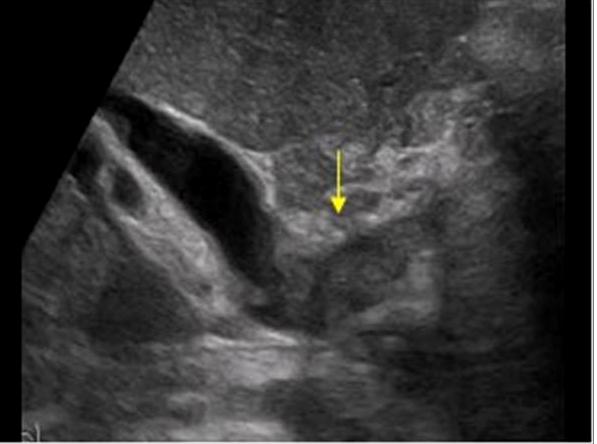

Mirizzi SYndrome

impacted stone in the cystic duct or GB neck

presence of two tubular structures representing the bile duct above the level of the cystic duct

Mirizzi SYndrome

impacted stone in the cystic duct or GB neck

presence of two tubular structures representing the bile duct above the level of the cystic duct